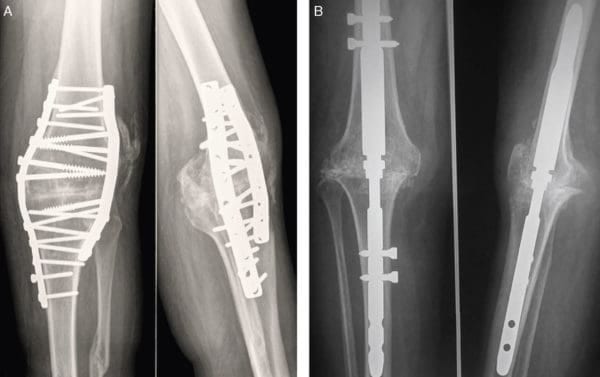

Если традиционная терапия не дает положительного эффекта или заболевание уже запущено, то без хирургической операции не обойтись. Существует несколько видов вмешательств:

- артродез. В этом случае удаляется не только деформированная ткань, но и сустав. Именно поэтому подвижность конечности практически не сохраняется. Из-за серьезных последствий для человека подобная операция проводится крайне редко;

- артроскопия. Такое вмешательство дает возможность избавиться от пораженной хрящевой ткани, при этом сочленение остается не тронутым. Весь процесс производится через небольшие проколы, через которые вводится специальное устройство – артроскоп и другие инструменты. Благодаря малой травматичности операции больной может полностью восстановиться за достаточно короткий срок. Несмотря на то что хирургическое вмешательство такого плана не является сложным, эффект от него продлится всего несколько лет;

- околосуставная остеомия. Эта операция считается очень сложной, поэтому проводится в редких случаях. Она предусматривает подпиливание костей в некоторых местах и их последующее соединение под необходимым углом. Это дает возможность перераспределить нагрузку. Эффект после операции длится не более 5 лет. Однако она эффективна только на ранних стадиях развития. Кроме того, данное вмешательство требует длительного периода восстановления;

- эндопротезирование. Эта операция производится в том случае, если сочленение или его элементы требуют полной замены. Протез изготавливается из сплава металлов – титана. Несмотря на то что операция требует длительного периода восстановления, эффект от нее весьма продолжителен – до 20 лет.